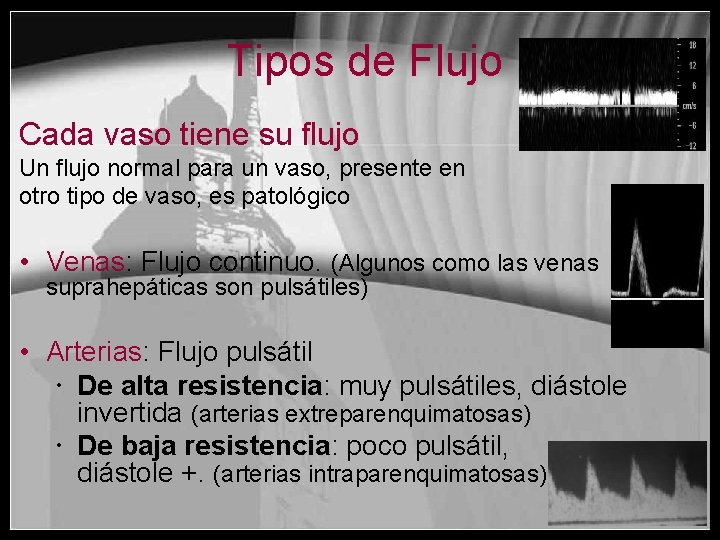

Tipos de Flujo Cada vaso tiene su flujo Un flujo normal para un vaso, presente en otro tipo de vaso, es patológico • Venas: Flujo continuo. (Algunos como las venas suprahepáticas son pulsátiles) • Arterias: Flujo pulsátil De alta resistencia: muy pulsátiles, diástole invertida (arterias extreparenquimatosas) De baja resistencia: poco pulsátil, diástole +. (arterias intraparenquimatosas)